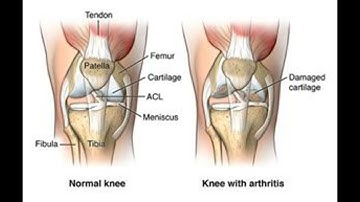

Arthroplasty with prosthetic replacement CPT code - simplify medical coding